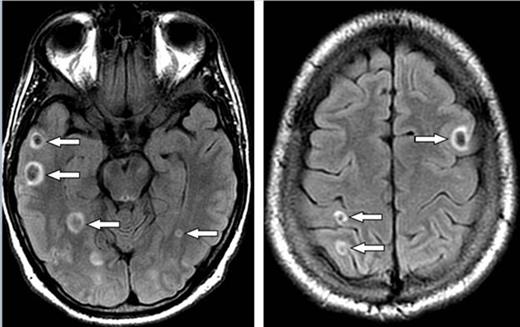

After admission, the patient developed headache and vomiting. MRI of brain showed multiple small hemorrhages in the supratentorial and infratentorial compartments (figure). The patient was diagnosed with accelerated-phase CML and leukostasis. Emergency leukapheresis was performed (two sessions) resulting in a decrease in his WBC count.

MRI brain FLAIR images show multiple ring like foci of recent hemorrhages (arrows).